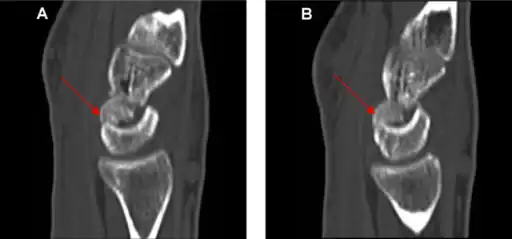

Typically they occur as a result of a fall on an outstretched hand or a direct blow to the back of the wrist.[1][2] Types include transverse body (most common), transverse pole, verticofrontal, and parasagittal.[1] Diagnosis is usually by X-rays.[1]

Diagnosis

Diagnosis is often by a posterior anterior wrist X-ray.[2]